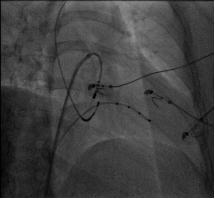

射频消融术是通过微创介入手段治疗心律失常的方法,是根治快速型心律失常的首选方法。经外周血管将直径2-3mm的消融导管送至心腔内,根据心内电生理检查结果定位消融部位,释放射频电流,导致局部心肌发生凝固性坏死,从而阻断快速心律失常异常传导束和起源点,达到根治心律失常的目的。经导管向心腔内导入的射频电流损伤范围在1-3 mm,安全有效。

治疗优势:手术在导管室施行的,不需要进行全身麻醉,不开刀、创伤小、恢复快、疗效确切、成功率高、并发症少;明显提高患者的生活质量,降低恶性心律失常的风险,已成为根治快速型心律失常的首选方法。

![`GJ3ECABFN)%]EGX~GAVBWB.png `GJ3ECABFN)%]EGX~GAVBWB.png](/Sites/Uploaded/Image/2016/03/246359443504518066405892408.png)

我院心血管中心拥有先进的DSA室、三维标测系统,已成功开展心内电生理检查、射频消融术、心脏起搏器植入术等治疗技术,治疗效果肯定,我们愿为广大患者竭诚服务。